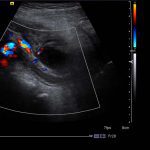

- Tubular, blind-ending structure in the right lower quadrant measuring 9 mm in diameter, which is noncompressible with mild wall thickening and mild mural hyperemia

- Superficial to this is a 2 x 2.5 cm ovoid hypoechoic structure which appears separate from the adjacent bowel and shows no internal vascularity

- An abscess should not have internal blood flow, but commonly will have peripheral hyperemia